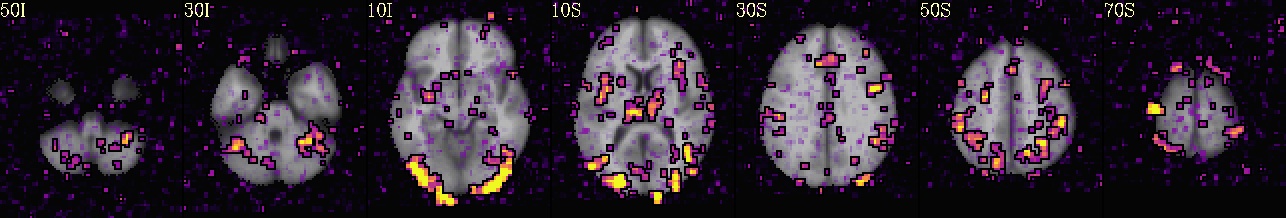

++ 3dmaskave: AFNI version=AFNI_21.2.00 (Jul  8 2021) [64-bit]

+++ 68948 voxels survive the mask

3dTcorr1D -prefix corr_brain errts.sub_08_REML+tlrc mean.errts.1D